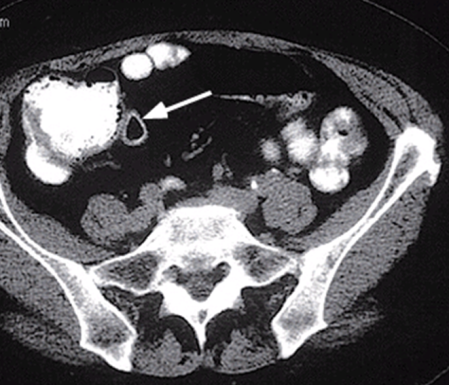

Mədə-bağırsaq sisteminin hissələrinin ikiləşməsinin 57%-ni təşkil edir. Əsas etibarı ilə ikiləşmənin qalça bağısaq lokalizasiyası müəyyən olunur (şək 5. ). Təcrid olunmuş ikiləşmə az təsadüf edir. Əksər hallarda digər bağırsaq anomaliyaları, üzvlərin və sistemlərin yanaşı anomaliyaları və inkişaf qüsurları ilə birgə rast gəlir.

Şək. 5. Nazik bağırsağın ikiləşməsi

Diaqnostika. Anamnestik məlumatlar (düz bağırsaqdan periodik qanaxmalar, residiv qarın ağrıları, nəcis ifrazının qəbizliyə meylliliyi), palpator kütlə əllənməsi, kontrastlı RH-ji və KT müayinələri (genişlənmiş proksimal (gətirici) bağırsaq ilgəyi, kontrastın haçalanması, kəskin hallarda üfuqi maye-qaz səviyyələri), laparoskopiya diaqnozun qoyulmasında çox mühümdür.